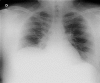

Cushing's syndrome occurred in 1-5% of cases of bronchial carcinoids. In this paper we describe a case of typical bronchial carcinoid in a nonsmoker young male with clinical manifestations mimicking a Cushing's syndrome. The patient performed chest radiograph and computed tomography. Fiberoptic bronchoscopy revealed the presence of an endobronchial mass occluding the bronchus intermedius. A rigid bronchoscopy was necessary for the conclusive diagnosis and for partial resection of the intraluminal tumor. Despite of the presence of Cushingoid features, the normal blood levels of ACTH and cortisol excluded the coexistence of a Cushing's syndrome.